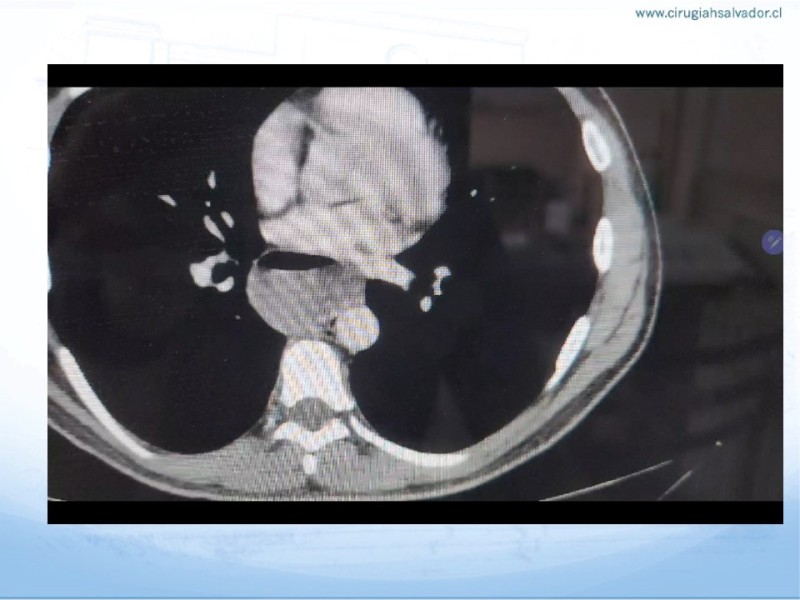

Acalasia

Digestivo Alto

| Autor: Dr. Byron San Martín García